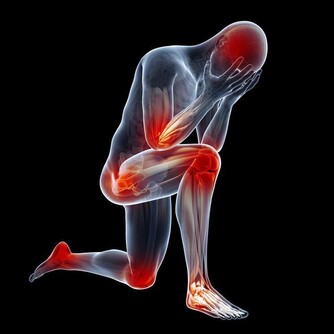

症狀3.除手指外,其他關節紅腫疼痛初步診斷:類風濕性關節炎

盧振和教授說,類風濕性關節炎,類似於過敏反應,與食物品種不當的攝取或環境污染等有較密切的關係。

除了手指關節外,肩腕、肘、膝等其他關節也經常會同時紅腫疼痛,而且會逐漸增生變形,痛感比較強。

應對方法:對症治療,避免吃深海魚、野味等非馴化的動物,以免產生過敏。手指疼痛的關節要注意保暖,以保證血流足夠的豐富和暢順。